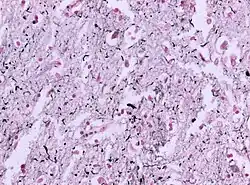

Otępienie z ziarnami argentofilnymi (ang. argyrophilic grain disease, AGD) – choroba neurodegeneracyjna wieku starczego należąca do grupy tauopatii, którą charakteryzuje obecność w badaniu neuropatologicznym bardzo licznych ziaren srebrochłonnych (argentofilnych) w pilśni nerwowej i ciał spiralnych w istocie białej. Jednostkę chorobową opisali jako pierwsi Heiko Braak i Eva Braak w 1987 roku. Częstość AGD nie jest znana, prawdopodobnie jej częstość w populacji jest wysoce niedoszacowana. Stosunkowo często pacjenci spełniają kryteria innych chorób neurozwyrodnieniowych: choroby Picka, zwyrodnienia korowo-podstawnego, choroby Olszewskiego-Richardsona-Steele’a, otępienia z ciałami Lewy’ego. Prawdopodobnie AGD może być pierwotną przyczyną otępienia i stanowić część obrazu neuropatologicznego innych chorób neurodegeneracyjnych.